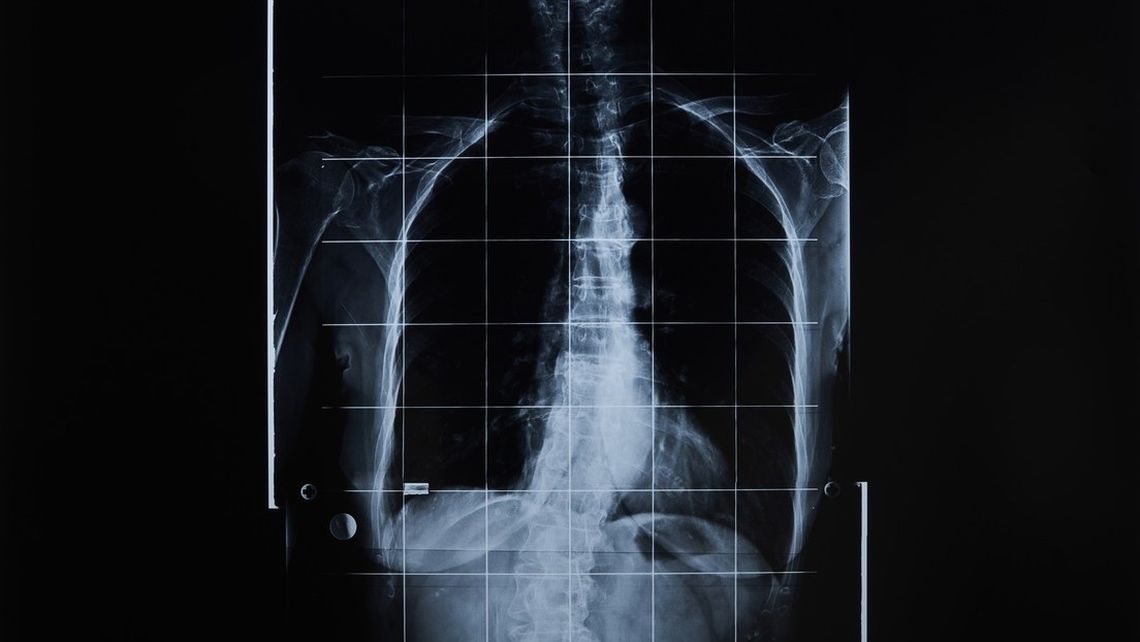

La startup pretende crear bolsas de órganos humanos no sensibles que puedan proporcionar sangre, tejidos y órganos a las personas cuando sus propios cuerpos les fallen.

Esta idea asoma como una promesa frente a la escasez crítica de órganos. Hoy, solo en Estados Unidos hay más de 100.000 personas en lista de espera y mueren 13 por día esperando un donante. Además, la propuesta busca combatir el mercado ilegal de órganos en Asia y África. Como las alternativas actuales, como el uso de órganos de cerdo modificados, no vienen dando buenos resultados (la supervivencia no llega a los nueve meses), en R3 Bio creen que es mejor "reemplazar que reparar". Boyang Wang, del fondo Immortal Dragons que financia el proyecto, fue directo: “Si podemos crear un cuerpo humano sin cabeza ni conciencia, será una gran fuente de órganos”.

Estos "sacos" serían superiores a los modelos de tejidos actuales o los órganos en chips, porque tendrían la complejidad real de un sistema vivo, incluyendo el riego sanguíneo. Aunque Gilman y su socio John Schloendorn negaron haber fabricado ya estos modelos en ratones y adelantaron que la estrategia combina edición genética con tecnología de células madre. La idea es usar células madre pluripotentes inducidas para transformar el tejido en cualquier órgano necesario.